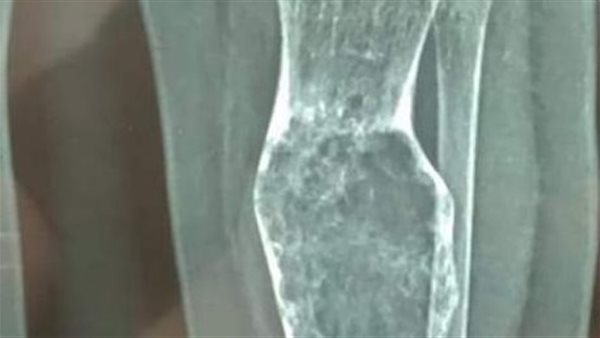

أعلنت الهيئة العامة للرعاية الصحية، نجاح قسم جراحة أورام العظام بمنظومة التأمين الصحي الشامل بمحافظة بورسعيد، من إجراء تدخل جراحي ناجح لرضيع يبلغ من العمر 9 أشهر، بواسطة جهاز الحفار عالي السرعة.

قام الفريق الطبي، بإجراء كحت لكيس ورمي لعظمة القصبة، وتم أخذ عينة منه وتنظيف الأنسجة الورمية داخل الكيس العظمي، مع المتابعة الدورية بواسطة جهاز الحفار عالي السرعة، وذلك داخل غرف عمليات المبرة.

أجرى الجراحة الدكتور محمد فاروق ذكي استشاري جراحة أورام العظام بمستشفى التضامن، والدكتور مصطفى محمد عبد العزيز أخصائي جراحة العظام بمستشفى التضامن، بمشاركة فريق التخدير الدكتور أحمد خميس استشاري التخدير بمستشفى التضامن.